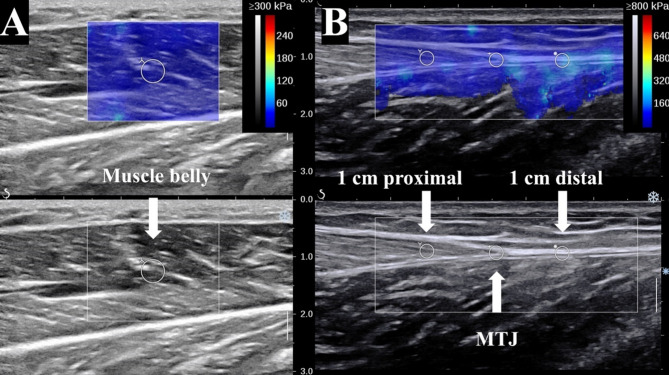

Methods: Ultrasound data were obtained from 22 calves, resulting in 44 samples, across three ankle positions: neutral, 15° plantarflexion, and 15° dorsiflexion, with the knee in an extended position. Young's modulus was sampled at the muscle belly, the MTJ, and proximal 1 cm and distal 1 cm on both side; each value represented the mean of three trials. Independent t-tests were employed to assess side-to-side differences, while one-way ANOVA (Bonferroni-adjusted, α = 0.05) was utilized to evaluate posture effects.

Results: Across neutral postures, the MG was stiffer than the LG at the muscle belly (P < 0.05), MTJ (P < 0.001), and at the distal 1 cm of MTJ. Dorsiflexion induced the highest stiffness values on both sides, with the MG demonstrating significantly greater stiffness than the LG (P < 0.05). Notably, despite its higher baseline stiffness, the MG showed a smaller contraction-induced percentage increase in stiffness compared to the LG at the MTJ in both plantarflexion (P < 0.05) and dorsiflexion (P < 0.05), indicating a high-stiffness/low-compliance (HNC) profile.